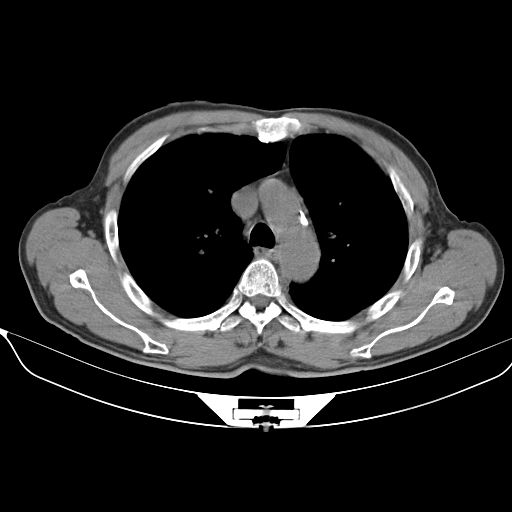

以下是引用心路寻觅在2010-3-1 10:23:00的发言:[br]1、考虑左肺上叶周围型肺癌[br]2、右上肺陈旧性病灶。[br][br][本贴已被 心路寻觅 于 2010-3-1 10:40:18 修改过]

以下是引用shuiyuan在2010-3-1 10:45:00的发言:[br]考虑左肺上叶中心型肺癌伴阻塞型炎症,邻近胸膜受侵。